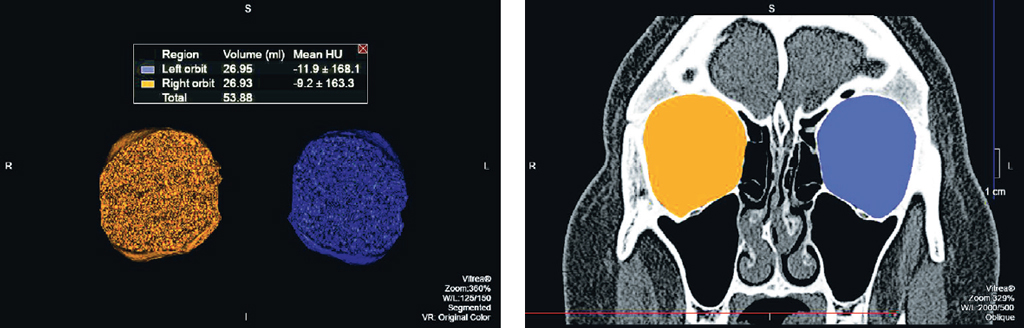

На каждом аксиальном срезе проводили маркировку всех костных границ орбит, начиная с верхней стенки до уровня дна орбиты с представлением объёмов орбит в миллилитрах. Для точности измерения чётко соблюдали костные границы и учитывали анатомические вариации строения обеих орбит (по методике расчёта объёмов орбит ранее был получен патент РФ «Способ оценки эффективности реконструктивной операции на орбите» RU2638623 C1, 14.12.2017. Бюл. № 35) (рис. 1).

Рис. 1. Мультиспиральная компьютерная томография. Обработка изображений для измерения объёмов орбиты: a — аксиальный срез, режим костного окна, маркировка костных границ обеих орбит; b — корональная реконструкция, режим костного окна, маркировка костных границ обеих орбит; c — 3D-реконструкция, объёмы правой и левой орбиты в математических единицах (мл)

Fig. 1. MSCT. Image processing for orbital volume measurement: a — axial section, bone window mode, marking of the orbital bone contours; b — coronal reconstruction, bone window mode, marking of the orbital bone contours; c — 3D-reconstruction, volumes of the right and left orbits in mathematical units (ml)

В результате проведённых исследований было установлено, что разница объёмов правой и левой орбиты 0,5 мл и более встретилась у 5 женщин из 25 случаев, среди мужчин разница была выявлена в 12 случаях из 25; разница объёмов более 1 мл была отмечена у 1 женщины и у 2 мужчин; разница более 1,5 мл не наблюдалась ни в одной исследуемой группе (рис. 2, 3).

Рис. 2. Мультиспиральная компьютерная томография. Обработка изображений для измерения объёмов орбиты. Объём правой орбиты 26,93 мл, объём левой орбиты 26,95 мл, разница составила 0,02 мл

Fig. 2. MSCT. Image processing for orbital volume measurement. The volume of the right orbit was 26.93 ml, the volume of the left orbit was 26.95 ml, the difference was 0.02 ml